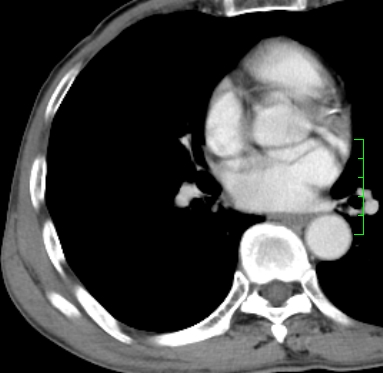

m,73y。膝关节疼痛伴双下肢水肿。入院常规胸片发现结节灶。增强为静脉期。

指套征,强化明显,近侧肺组织局限性肺气肿,考虑支气管类癌,慢支、肺气肿、双上陈旧性tb、冠脉钙化。

1)考虑右肺下叶周围型肺癌。2)右肺上叶及左肺感染性病变(结核可能)。3)肺气肿。4)冠状动脉钙化。